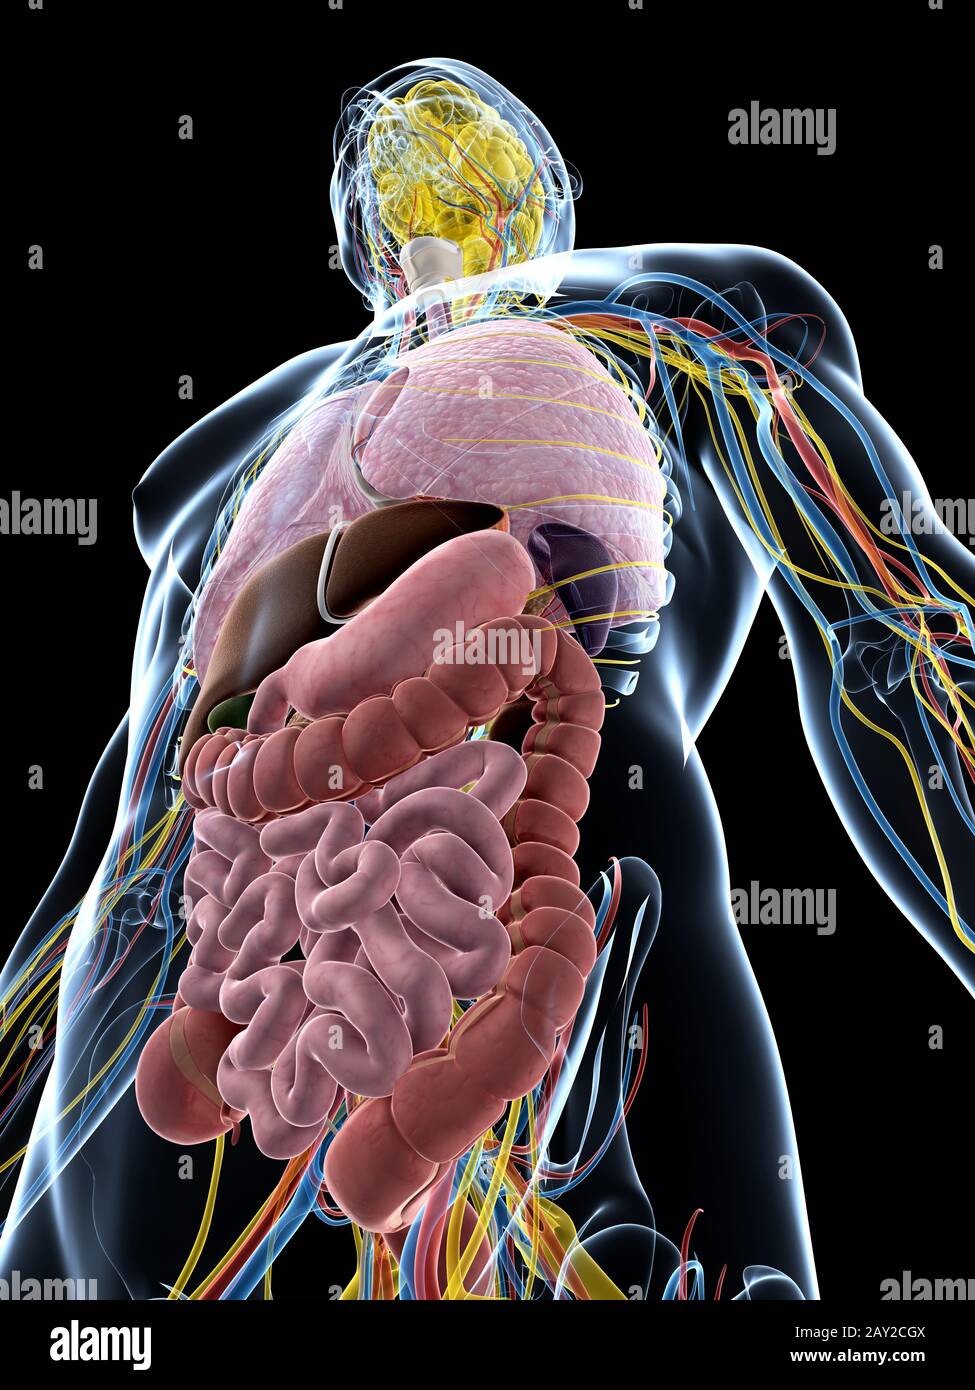

RF2GB8D4J–3D-Darstellung des Verdauungssystems der männlichen Anatomie, zusammen mit anderen inneren Organen. Glasbild auf blauem Hintergrund, Vorderansicht.